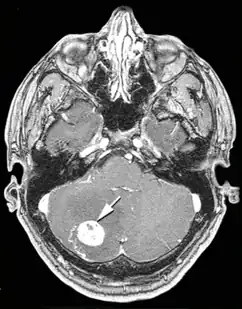

Гемангиобластомы головного мозга

Узел гемангиобластомы состоит из клубка тонкостенных сосудов. При введении в кровь контрастных веществ опухоль накапливает вводимые препараты, благодаря чему хорошо контрастируется на ангиограммах, компьютерных и магнитно-резонансных томограммах. Определяются крупные патологические артерии и вены, могут выявляться артерио-венозные шунты[18]. При проведении компьютерной (КТ) и магнитно-резонансной (МРТ) томографий диагностируются две формы опухоли — узел с или без кистозного компонента. Первая форма характеризуется тем, что большие кисты выполняют большую часть объёмного образования. Узел может вообще не определяться с помощью нейровизуализационных методов исследования[18].

Киста гемангиобластом обычно округлой или овальной формы, на компьютерной томографии имеет низкую плотность (8—14 единиц Хаунсфилда). При введении контрастных веществ плотность её содержимого и стенок не изменяется. Узел опухоли определяется на КТ в виде очага повышенной плотности, чаще негомогенной зернистой структуры. Располагается на одной из стенок кисты, вдаваясь в её просвет, хорошо накапливает контрастное вещество[18].

При кистозной форме опухоли на магнитно-резонансных томограммах хорошо определяется кистозный компонент, который характеризуется низкой интенсивностью сигнала на Т1- и высоким сигналом на Т2-взвешенных томограммах. На этом фоне хорошо визуализируется пристеночно расположенный солидный узел гемангиобластомы, хорошо накапливающий контрастное вещество[18].

При солидной форме гемангиобластомы в строме новообразования отмечается наличие округлых и извитых участков потери сигнала за счёт кровотока в крупных сосудах опухоли[18].